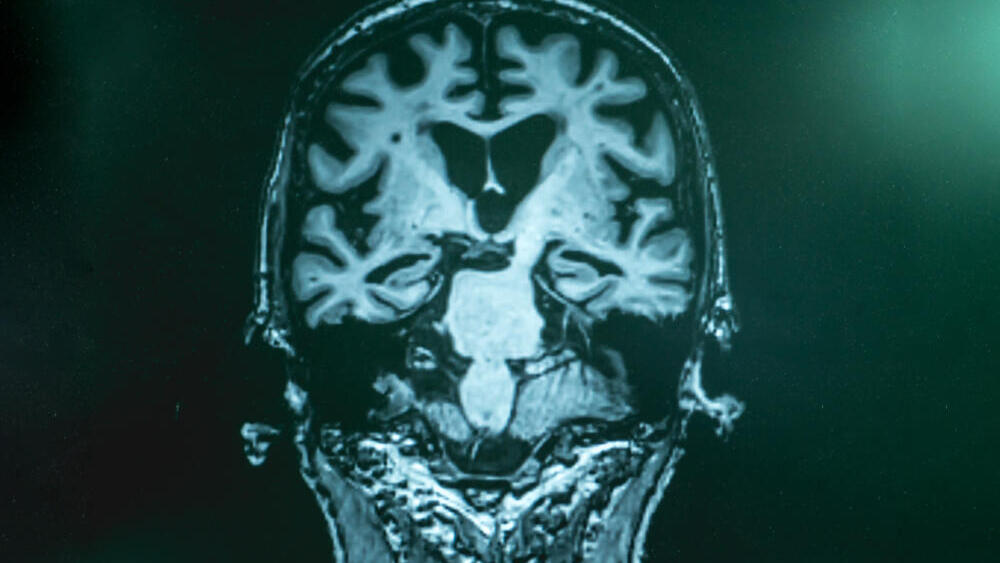

Alzheimer's disease is a severe neurodegenerative condition that impairs memory and cognitive function. The risk of developing the disease increases with age, affecting as many as one in three people aged 85 and older. Despite extensive research, the exact causes of Alzheimer's remain unclear, and effective treatments remain elusive.

Until recently, much of the research in the field focused on two primary factors: accumulation deposits of a protein called amyloid beta between neurons in the brains of affected individuals, and the formation of neurofibrillary tangles composed of a protein called tau that become trapped inside the neurons.

These two components are commonly found in the brains of patients, constituting primary biomarkers of the disease. The prevailing theory suggests that they contribute to the degeneration of nerve cells and the decline in brain function. Alois Alzheimer first documented their presence in patients' brains when he defined the disease over a century ago, in 1906.